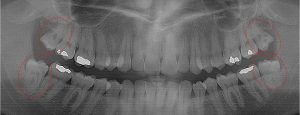

This 34 year old patient has all four third molars present (circled) and fully erupted into occlusion. They appear disease free…but are difficult to keep clean. 3rd molars are the most likely teeth to decay or have gum disease with a >98% probability that decay and gum disease will occur around all four teeth over this patient’s life time.